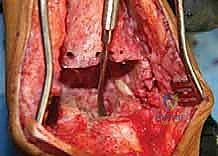

يتم فتح الشق الجراحي الأمامي القديم بحذر شديد لتجنب إتلاف الأوعية الدموية والأعصاب، وهنا تبرز أهمية تقنيات الجراحة الميكروسكوبية التي يتقنها الدكتور هطيف.

الخطوة الثالثة: إزالة المفصل القديم (Explant Removal)

يتم استخراج المكونات المعدنية والبلاستيكية لمفصل (Agility) القديم بحرص بالغ للحفاظ على ما تبقى من العظم السليم.

الخطوة الرابعة: تنظيف العظم والترقيع (Debridement and Bone Grafting)

يتم تنظيف الأنسجة الملتهبة والأكياس العظمية. ونظراً لأن مفصل (Agility) يترك فراغاً كبيراً بعد إزالته، يتم استخدام طعوم عظمية (Autograft من حوض المريض أو Allograft من بنك العظام) لملء الفراغات وبناء أساس قوي.